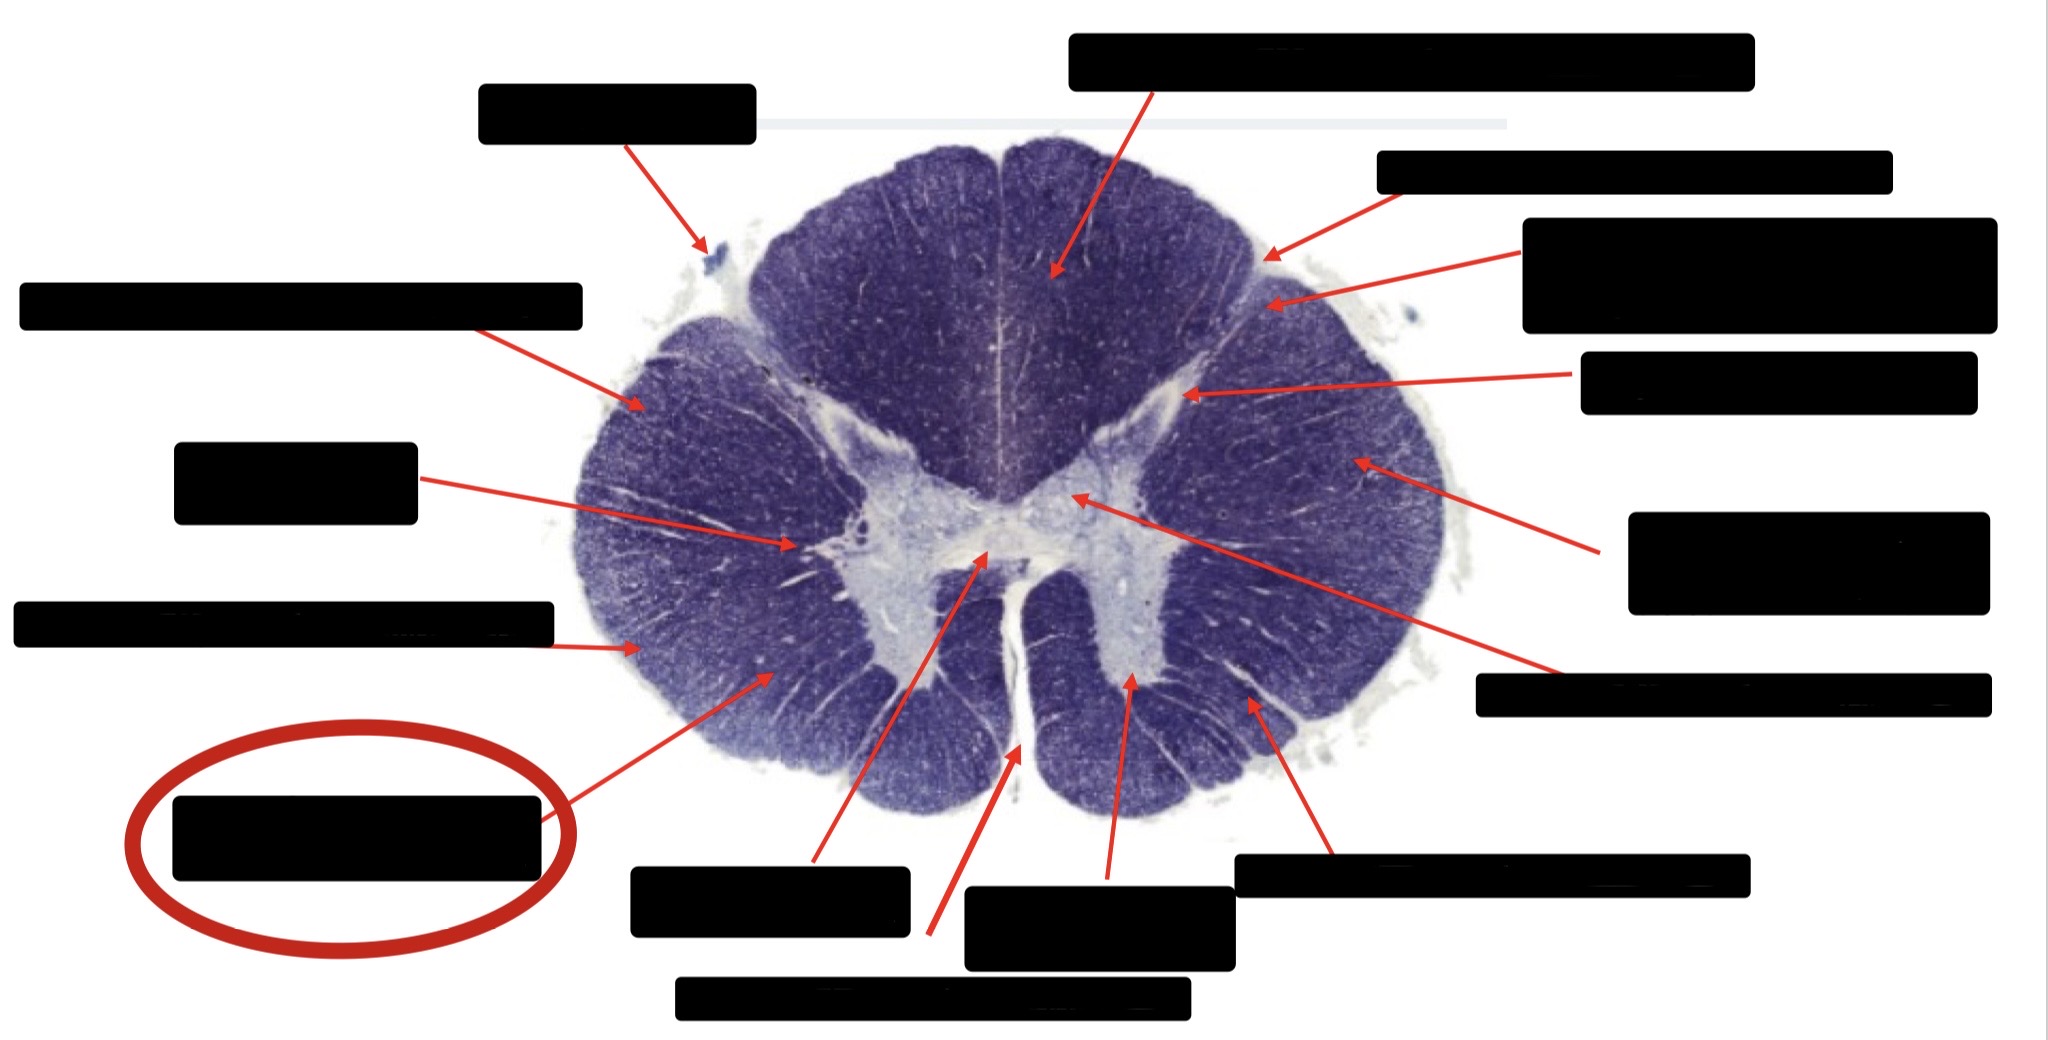

Posterior Column (Fasciculus Cuneatus)

Substantia Gelatinosa

Anterior Horn Motor Neurons (Distal Muscles)

Anterior Horn Motor Neurons (Proximal Muscles)

Ventral Root Fibers

Central Canal

Anterior Corticospinal Tract

Large Fiber Entry Zone

Dorsal Rootlet

Posterior Spinocerebellar Tract

Lateral Corticospinal Tract

Anterior Spinocerebellar Tract

Spinothalmic Tract

Posterior Column (Fasciculus Gracilis)

Accessory Nerve Fibers

Anterior Horn Motor Fibers (Accessory Muscles)

Anterior Horn Motor Fibers (Proximal Muscles)